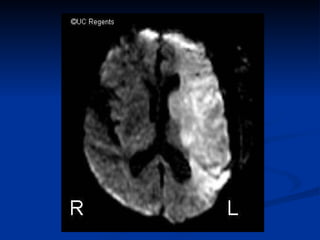

Tipos de AVC

• 5.